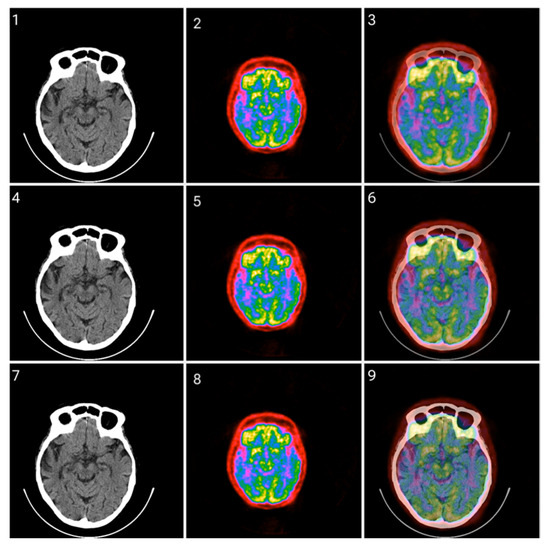

3.1. CIT Application

3.2. Colormap Folding Application